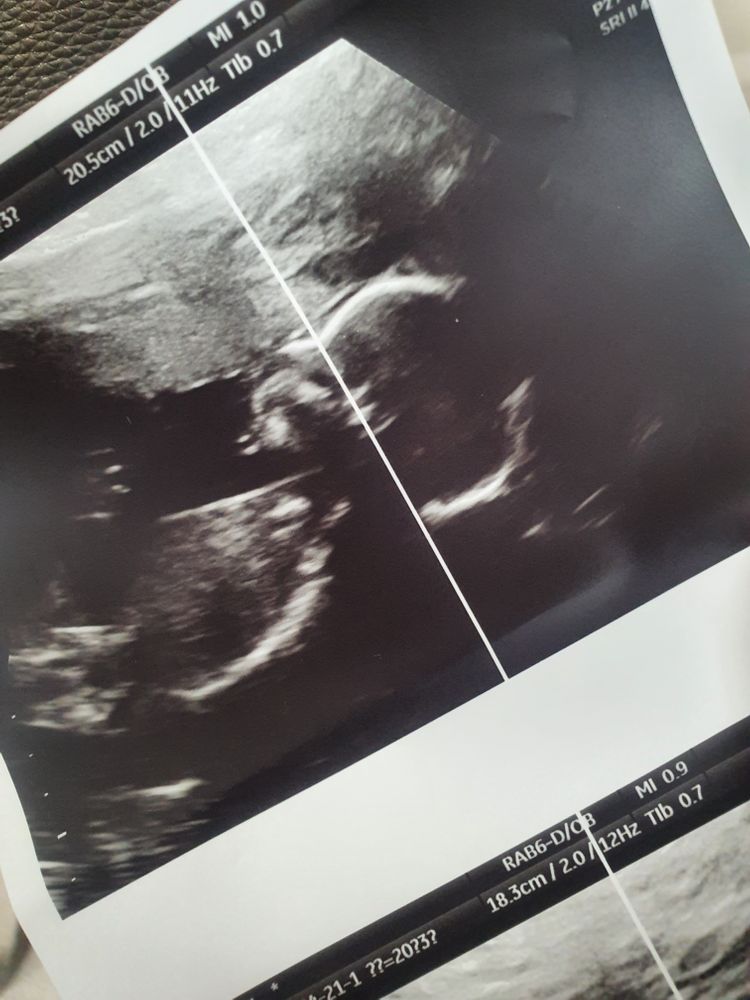

Прошли 2й скрининг, ждём мальчика🥰 Но есть пара вопросов...

В 20+4 прошла 2й скрининг, сказали,что мальчик 100%,уже ничего не отвалится🤣 Но есть некие странности. Перед этим была на узи в почти 17 недель,ходила,чтобы посмотреть пол. В заключение написано " Пуповина имеет 3 артерии". Кровоток не нарушен. Шов 5.6 мм(было экс 2 года назад). А сегодня на узи 2 артерии только и шов 1.8мм. И вот я теперь не понимаю,какому врачу верить?(была в двух разных клиниках платно). Если шов ещё может теоретически так истончится,но артерия в пуповине не могла же деться никуда? Оба узиста считаются лучшими в городе и аппараты тоже хорошие.